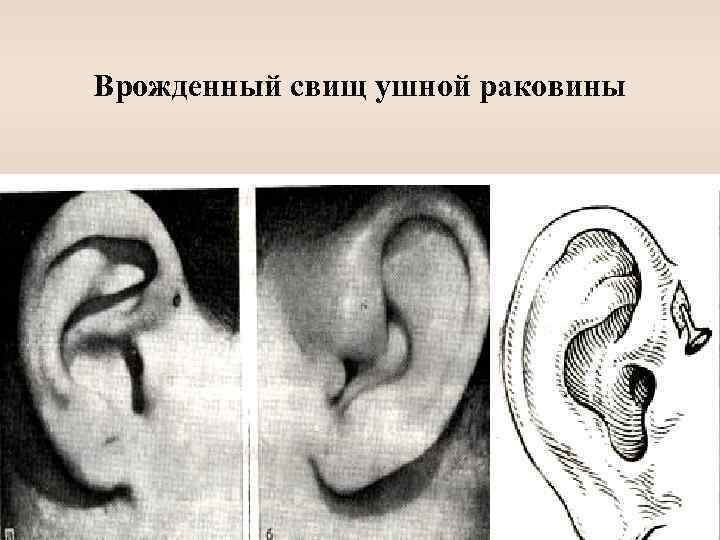

Синдром 1 жаберной щели ü Ушные придатки ü Врожденные свищи ü Шейно-ушные фистулы

Врожденный свищ ушной раковины